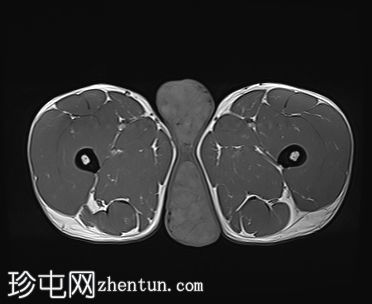

轴位

T1加权像

阴囊内睾丸增大,T1加权像上可见分叶状软组织病变,呈中高信号,T2加权像上呈低信号。

轻度双侧鞘膜积液。

本病例表现为双侧睾丸肿胀,影像学特征符合睾丸肾上腺残余肿瘤的典型表现,即T1加权像上呈双侧中高信号,T2加权像上呈低信号。